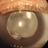

- posterior chamber intraocular lens (PCIOL)

- A pseudophakic patient visiting after 6 months of cataract surgery. On slit lamp examination a complete hazy white PCIOL was seen, which is a rare complication after cataract surgery.